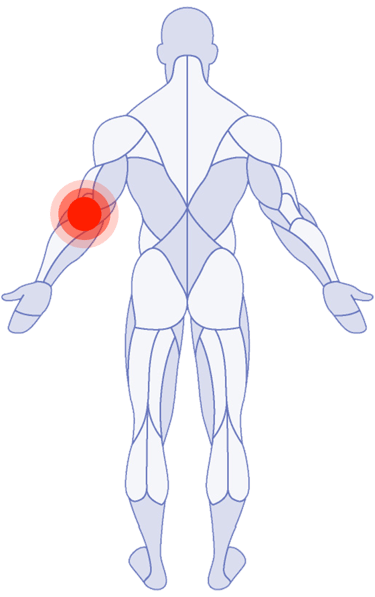

Where Do You Need Attention?

Use the latest research in physical therapy to work better, play better and spend more time on what really matters.

Shoulder Pain